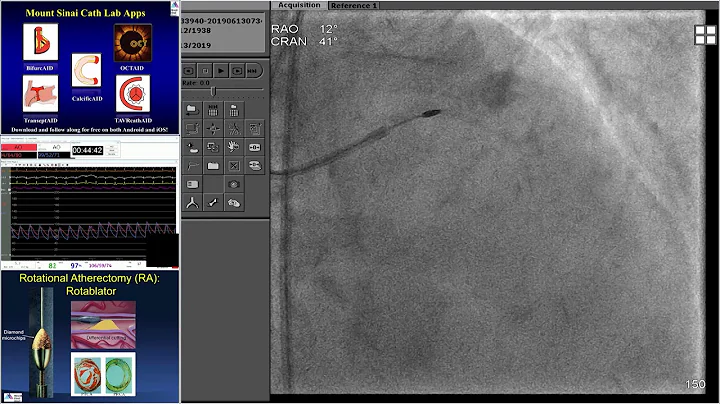

Expanded Indications Of Impella: Protected Pci - Dr. Lasala